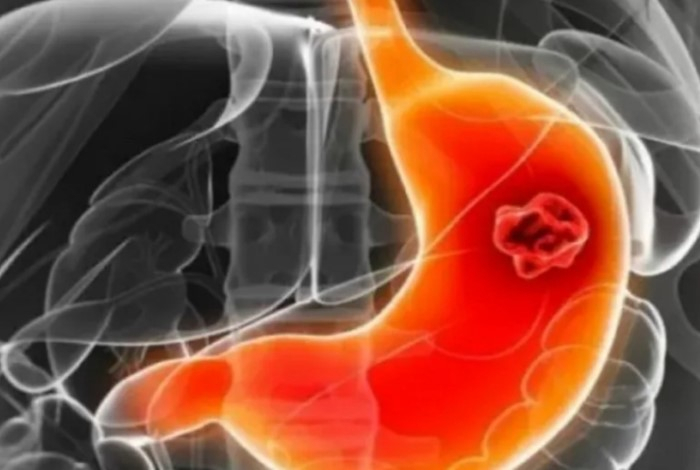

Основной причиной возникновения различных заболеваний желудка врачи называют бактерию Helicobacter pylori. При этом встречается она практически у каждого второго человека. Установлено, что именно эта бактерия является основной причиной гастрита и онкологии, а вовсе не те продукты, которые употребляет человек,...